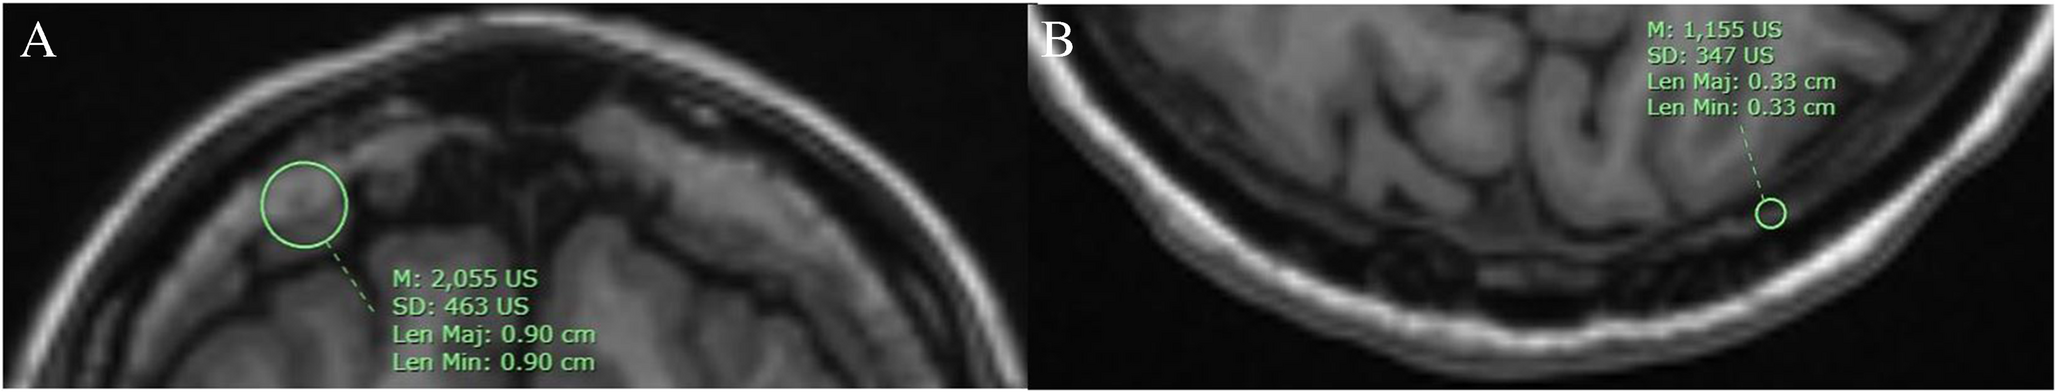

MRI evaluation of hyperostosis frontalis interna: differentiation and diagnostic insights

To delineate the MRI characteristics of Hyperostosis Frontalis Interna (HFI) and evaluate its imaging features to aid in a...